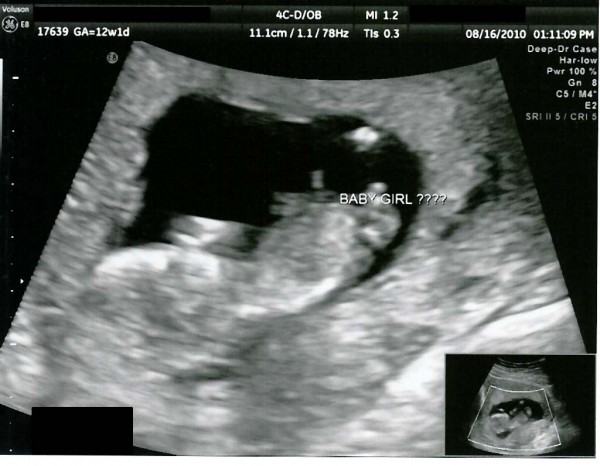

So I'm still pregnant.. yay 3 weeks past the point of my miscarriage, and 100% different than the last pregnancy.. there's actually a baby in there I'm 12 weeks and 3 days along. My due date is February 27...aaaaand it's a GIRL!! Pretty sure at least. I had an ultrasound on Monday and the doctor is 80% sure it's a girl. I think he's going by a gender theory, but he's the professional, and I have a strong feeling it's a girl anyway. So do a few other people.. except my mom, but that's a good indication that it really is a girl, because she has never been right!

Here's a picture of my little peanut